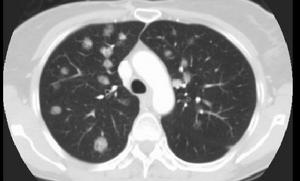

其它輔助檢查: 1.X線檢查 X線胸片所見依病變進展時期而不同典型者表現示兩肺中、下葉有多發性結節狀陰影大小不一,直逕自數毫米至10cm不等,1/3伴有厚壁空洞形成,20%左右僅為單側肺結節陰影。少數表現為肺大片浸潤性陰影1/3可見胸膜腔積液。但肺門淋巴結不腫大。偶爾可見兩肺呈瀰漫性網狀結節性和絨毛狀肺泡浸潤或呈多發性結節性病變,類似於轉移性肺癌病變多為雙側性,主要累及兩下肺野,特別是兩肺外帶結節影可迅速增大或縮小而且甚至可以完全消失。少數患者有縱隔或肺門淋巴結腫大